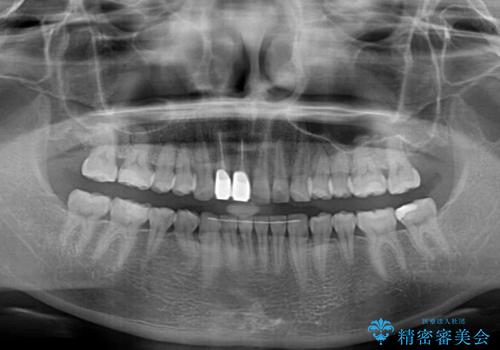

- 一度矯正治療を希望して始めたものの断念し、前歯をセラミッククラウンで治療した後に、やはり矯正でしっかり治したいとのことで来院された患者様です。

当初、前歯の歯列矯正を希望して銀座院に来院され、補助装置を装着するところまで進んだのですが断念してしまいました。

その後、他院で気になる前歯をセラミッククラウンで補綴治療をしたそうですが、やはり歯列を整えたいとのことで再度来院されました。

クラウンの状態は、根管治療の状態も含めて決して良い状態とは言えず、矯正治療後の根管治療と補綴治療の再治療を前提として、インビザラインによる矯正治療を行うこととしました。